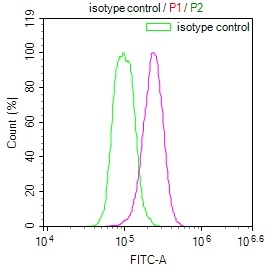

The image on the left is immunohistochemistry of paraffin-embedded Human breast cancer tissue using CSB-PA919263(SPAG4 Antibody) at dilution 1/25, on the right is treated with synthetic peptide. (Original magnification: ×200)